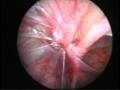

Torsion of Left Undescended Testis (Pre operative and Operative Photo)

Of the many causes of acute scrotum, the most common and important is Torsion of Testis. The testis is supplied by a single blood vessel and any torsion on this vessel may impede the blood supply to the testis. If urgent medical attention and intervention is not done, this may result in testicular gangrene and orchidectomy ( removal of the dead testis) may be needed.

The commonly misleading history given by the parents is that the child may have had a trivial trauma or an insect bite. However, for the clinician the golden rule should be ‘Any acute scrotum is testicular torsion unless proved otherwise’. Investigations like ultrasound and color doppler may be done to help in the diagnosis. However, in the event of any doubt, it is safest to do a surgical exploration of the scrotum. The other uncommon causes of acute scrotum are acute epidydymo orchitis, scrotal abscess, idiopathic scrotal oedema and torsion of appendix of the testis. ●